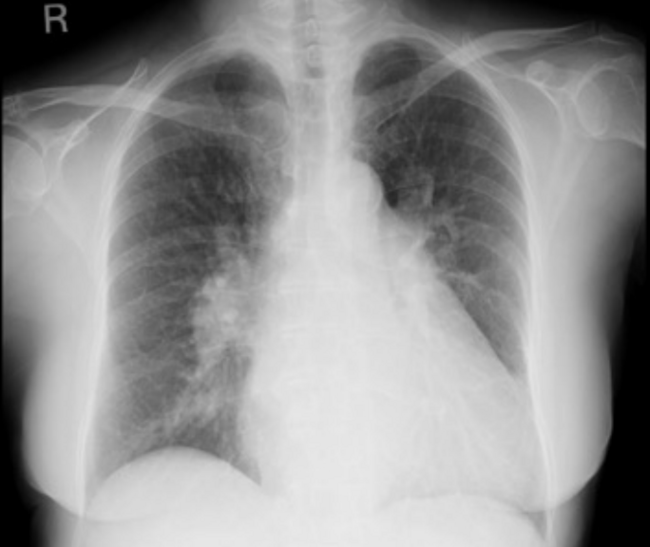

This patient was a 67-year-old woman who had been caught in a cultivator and had her right leg amputated in the 1980s. She had no medical history of congestive heart failure or shortness of breath. She was administered direct oral coagulant, a β-blocker, and a proton pump inhibitor because of chronic atrial fibrillation. Twenty-seven years after the accident, she presented to our hospital because of a swollen left leg and shortness of breath. Her blood pressure was 125/82 mmHg, heart rate was 100/min with atrial fibrillation, and saturation was 95% in room air. The results of a complete blood test as well as renal, liver, and thyroid function tests were all normal but the serum BNP level rose to 607.1 pg/mL. Chest radiography confirmed cardiac dilation, pulmonary congestion, and pleural effusion (Figure 1). She was given 20 mg/day furosemide to treat congestive heart failure. We confirmed a bruit at her left groin and pulsations in a lower leg vein. Transthoracic echo cardiography (TTE) showed an ejection fraction of 55%, her right ventricular pressure increased to 44 mmHg, and severe tricuspid valve regurgitation was detected. Vascular echo showed an arteriovenous fistula (AVF), shunt flow, and an expanded femoral vein (Figure 2). A computed tomography (CT) angiography was performed and revealed a left medial femoral circumflex artery (MFCA)–left common femoral vein (CFV) fistula (Figure 3).